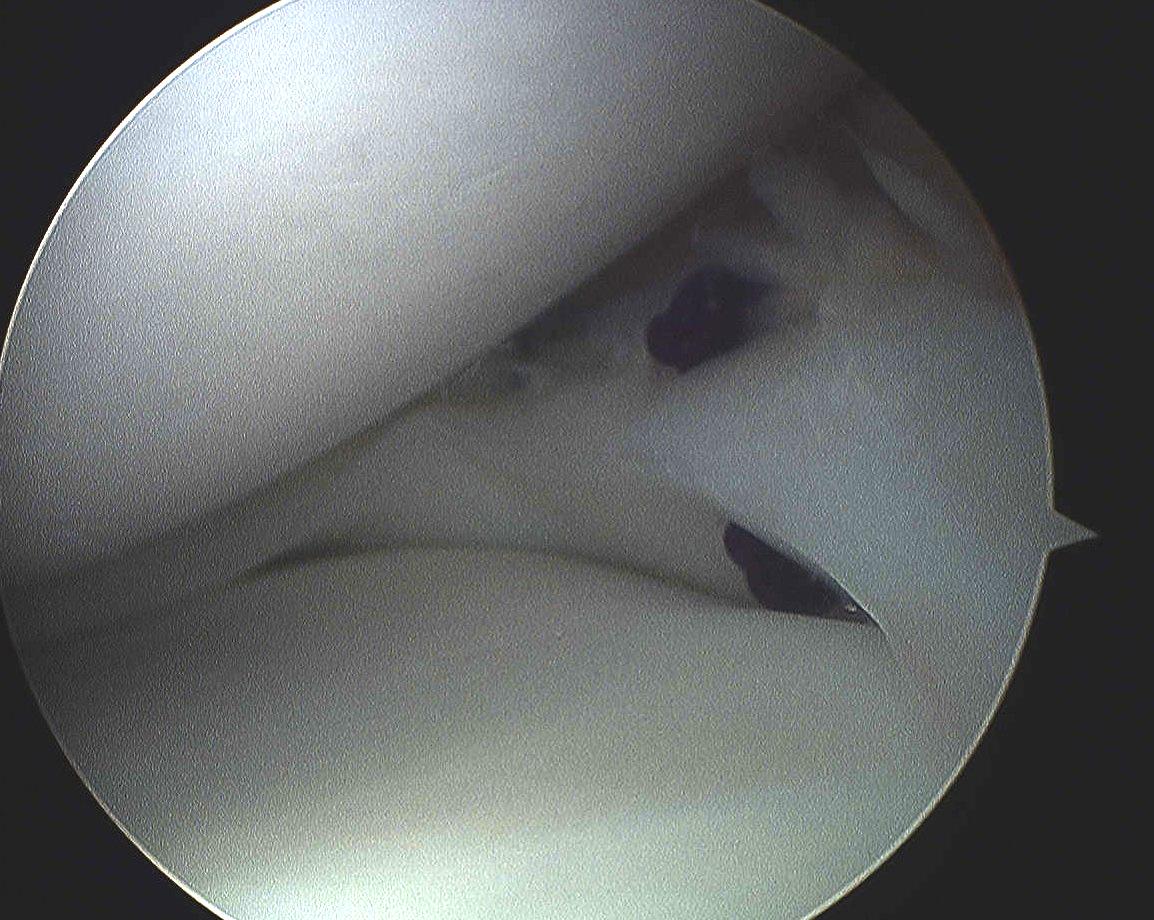

1. Red / Red longitudinal tear

- outer 3mm / meniscocapsular junction

2. Red / White longitudinal tear

- only one side of tear vascularised

Ramp lesion